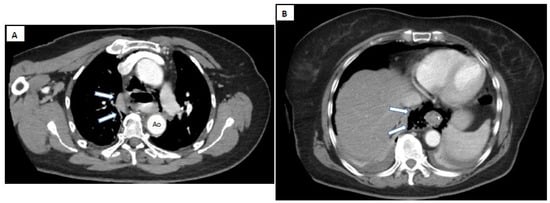

- Pneumomediastinum

- Pneumothorax (especially left-sided)

- Pleural effusion (especially left-sided)

- Localized periaortic gas

- Mediastinal fluid collections

- Thickened esophageal wall

- Gas within thoracic soft tissues, neck, or around major vessels

- Gas in the epidural space

- Pneumoperitoneum

- Gas in the retroperitoneal space

- Oral contrast extravasation from the esophageal lumen [10].